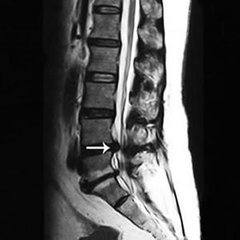

随着人的年龄的增长,身体的机能也会出现退化,总是会有这样那样的并会出现,其中像骨病是较为突出的,像腰椎间盘突出、腰椎管狭窄等都会出现。这类骨病危害很大,腰痛、乏力、腰腿麻木、竞争性不行等都是常见的症状。那么,椎管狭窄会有哪些危害呢?下面就和大家介绍一下。 >>>椎管狭窄的症状有哪些你了解吗?

走不动路便是腰椎管狭窄的危害之一,也是较具代表性的症状。腰椎管狭窄多见于中老年,男性居多,多体现为慢性或复发性腰背痛有时伴有坐骨神经痛。腰过伸运动时痛苦加剧。痛苦继续数月致使数年进而出现典型的间歇性跛行。 >>>椎管狭窄的预防要从什么时候开始?如何预防?点击咨询

在久站或行走一段后因为腰椎伸直脊柱前凸,使神经根受压加剧或因神经细胞需氧量增加而呈相对缺氧情况,因而惹起下肢麻痹肌痉挛痛苦和跛行在歇息或折腰后,神经根受压和神经缺氧情况好转痛苦消逝。神经系统体征有下肢肌力削弱,肌肉萎缩,感觉反射反常和大小便功用妨碍。感觉妨碍出现一般迟于运动妨碍。 >>>我的这些症状严重吗?该怎么治疗较好?